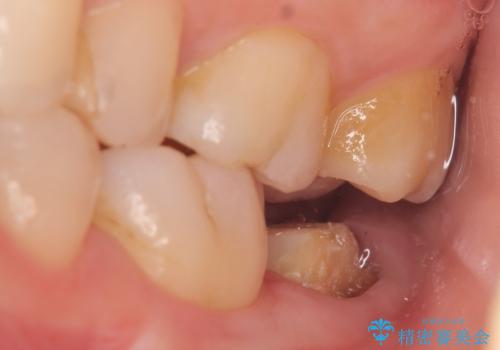

- 左下の一番奥の歯が時折激しく痛むので診て欲しいといらっしゃった方の症例です。以前に他院を受診したところ、そもそも被せ物を入れるスペースがないため抜歯しかないと言われたとのことでした。

診査の結果根尖病変を認めたため再根管治療を行った後に、被せ物を入れるスペースを作るため歯冠延長術を行いました。

今回用いたオールセラミッククラウンはジルコニアフレームという白い素材の上にセラミックを盛っているため、審美性が非常に高いのが特徴です。

また、ジルコニアは人工ダイヤモンドの材料にも使われているほど高い強度を持っており、そのためオールセラミッククラウンは審美性だけでなく、奥歯やブリッジの補綴も可能とするクラウンです。

歯冠延長術について

歯冠長延長術とは歯肉弁根尖側移動術とも言い、歯の高さが低くクラウン(被せ物)による治療が難しい場合に、歯茎を歯根方向に下げることで歯の高さを確保する手術です。歯の高さが十分にあることで、外れにくいしっかりとしたクラウンを被せることができます。